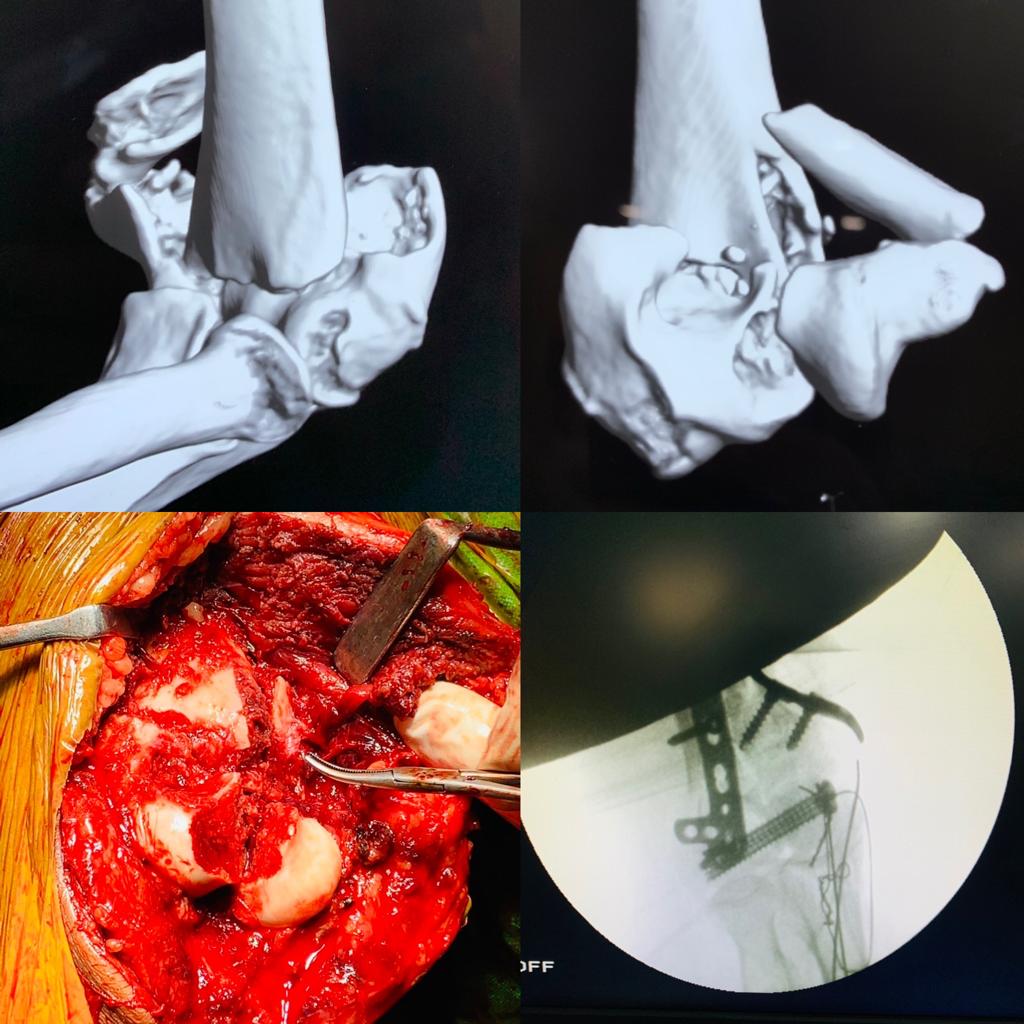

Complex Distal Humerus Comminuted Fracture

Complex Distal Humerus Comminuted Fracture

Complex Distal Humerus Comminuted Fracture

Complex Distal Humerus Comminuted Fracture

Complex Distal Humerus Comminuted Fracture

Complex Distal Humerus Comminuted Fracture

Complex Distal Humerus Comminuted Fracture

Complex Distal Humerus Comminuted Fracture

Complex Distal Humerus Comminuted Fracture

Complex Distal Humerus Comminuted Fracture

Complex Distal Humerus Comminuted Fracture

Complex Distal Humerus Comminuted Fracture

Complex Distal Humerus Comminuted Fracture

Complex Distal Humerus Comminuted Fracture